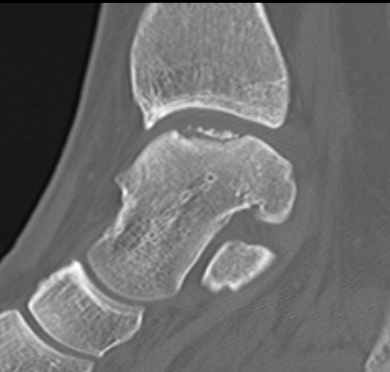

Fracture anterior process of calcaneum